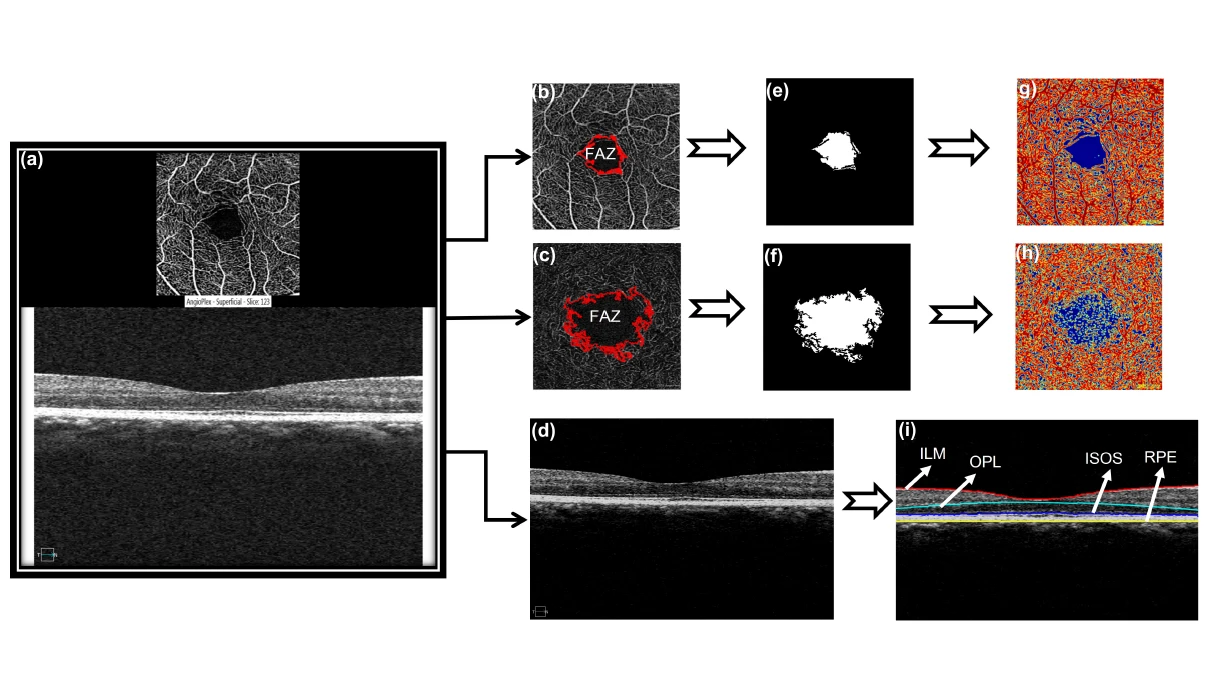

The lab has also serially evaluated epithelial remodelling following procedures such as LASIK, SMILE, and PRK, and quantified micro-distortions in the Bowman’s layer to support the identification of asymmetric keratoconus. In retinal imaging, the lab has developed automated algorithms to quantify OCT images in glaucoma and diabetic retinopathy, evaluated posterior vitreous visibility using enhanced depth and vitreous imaging techniques, and conducted extensive OCTA vascular comparisons across devices, finding significant correlations between macular edema volume and retinal features in patients with diabetes. IBMS also pioneers Polarization-Sensitive OCT (PS-OCT), which captures birefringence, a key biomarker for early disease detection, to reveal microstructural details invisible to conventional OCT. In parallel, IBMS is developing Cellular-Resolution OCT to visualise corneal structures at near-microscopic detail in real time, without contact or anaesthesia, bridging the gap between clinical imaging and laboratory microscopy.